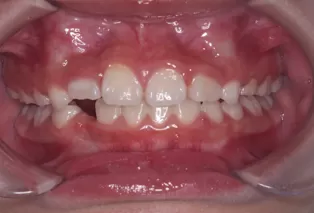

Photos intra-orales